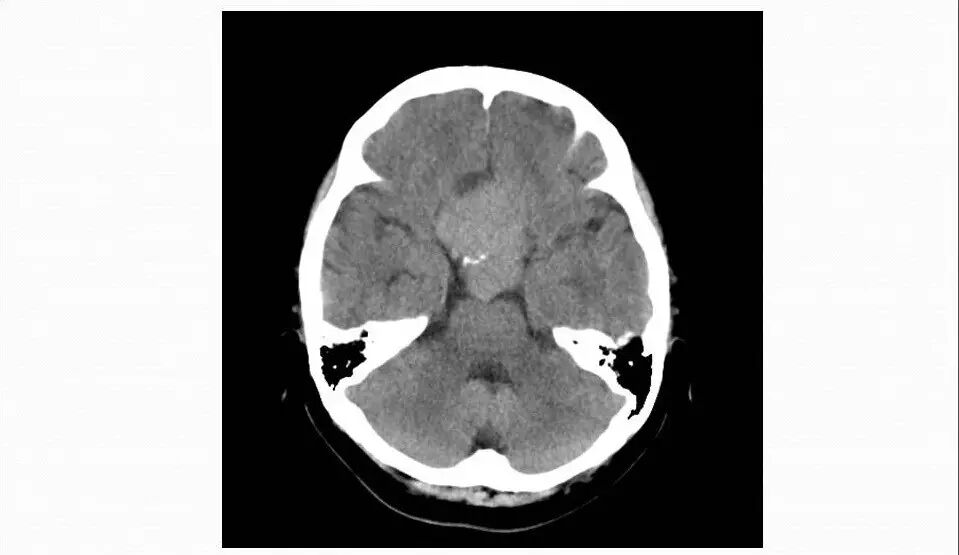

3.CT检查显示肿瘤呈等密度影,可见鞍背骨质破坏;

4.重点观察冠状位:病变源于垂体偏左侧,与垂体界限不清楚,肿瘤偏右侧可见垂体与肿瘤之间裂隙,造成矢状位平扫及强化后误认为正常垂体存在,从而首先除外了垂体瘤,导致误诊;